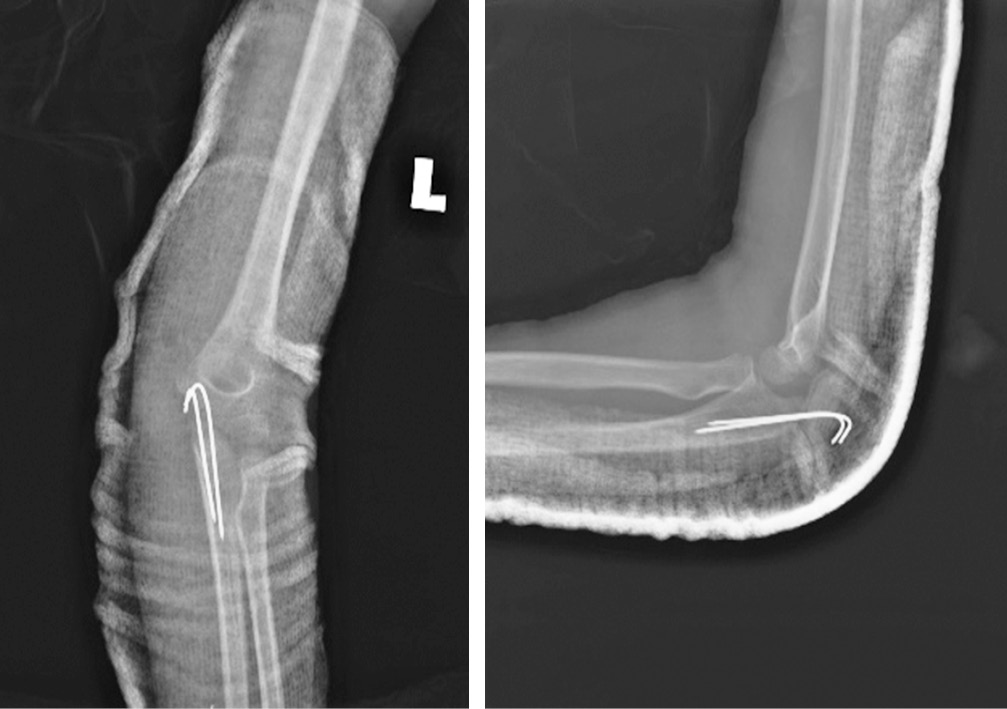

На обзорной рентгенограмме левого локтевого сустава выявлен передний вывих с переломом локтевого отростка (рис. 1). Примерно через два часа после травмы в отделении скорой помощи была предпринята попытка закрытого ручного устранения вывиха, которая оказалась неуспешной. Приблизительно через 6 ч после травмы под общей анестезией выполнено открытое устранение вывиха с чрескожной фиксацией спицей Киршнера. Для ревизии локтевого нерва и репозиции перелома выбран медиальный доступ. Интраоперационно обнаружено ущемление локтевого нерва дистальным фрагментом локтевой кости несколько дистальнее борозды медиального мыщелка. Нерв был натянут, его цвет казался слегка бледным, но целостность была не нарушена. Лучевой нерв был мобилизован проксимально и дистально до исчезновения натяжения. Перелом локтевого отростка произошел в области метафиза, при этом отломок кости был прикреплен в метаэпифизарной зоне, что соответствовало перелому II типа по Salter-Harris. Для репозиции выполнена осторожная контролируемая тракция за локоть. Перелом фиксирован двумя параллельными спицами Киршнера, репозиция головки лучевой кости была спонтанной. Полностью разорванная медиальная коллатеральная связка была восстановлена с помощью рассасывающейся нити 5/0. Интраоперационно оценена стабильность: локтевой сустав был стабилен в супинации, пронации, сгибании и разгибании. После репозиции и восстановления мягких тканей определялась хорошая пульсация на плечевой, лучевой и локтевой артериях. С помощью лонгеты локтевой сустав иммобилизован под углом 90° с предплечьем в положении супинации (рис. 2).

Рис. 1. Обзорная рентгенограмма левого локтевого сустава, на которой виден передний вывих в локтевом суставе с сопутствующим переломом локтевого отростка